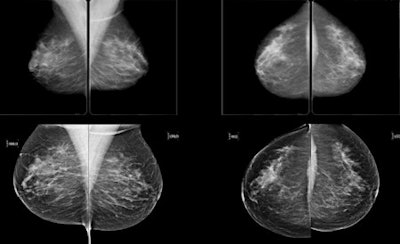

Subtle mass that was not recalled during screening, but detected on CAD. Top row: Exams that were not recalled during screening. Bottom row: Exams where lesion was detected in a later screening round. All images courtesy of Dr. Jaime Melendez.